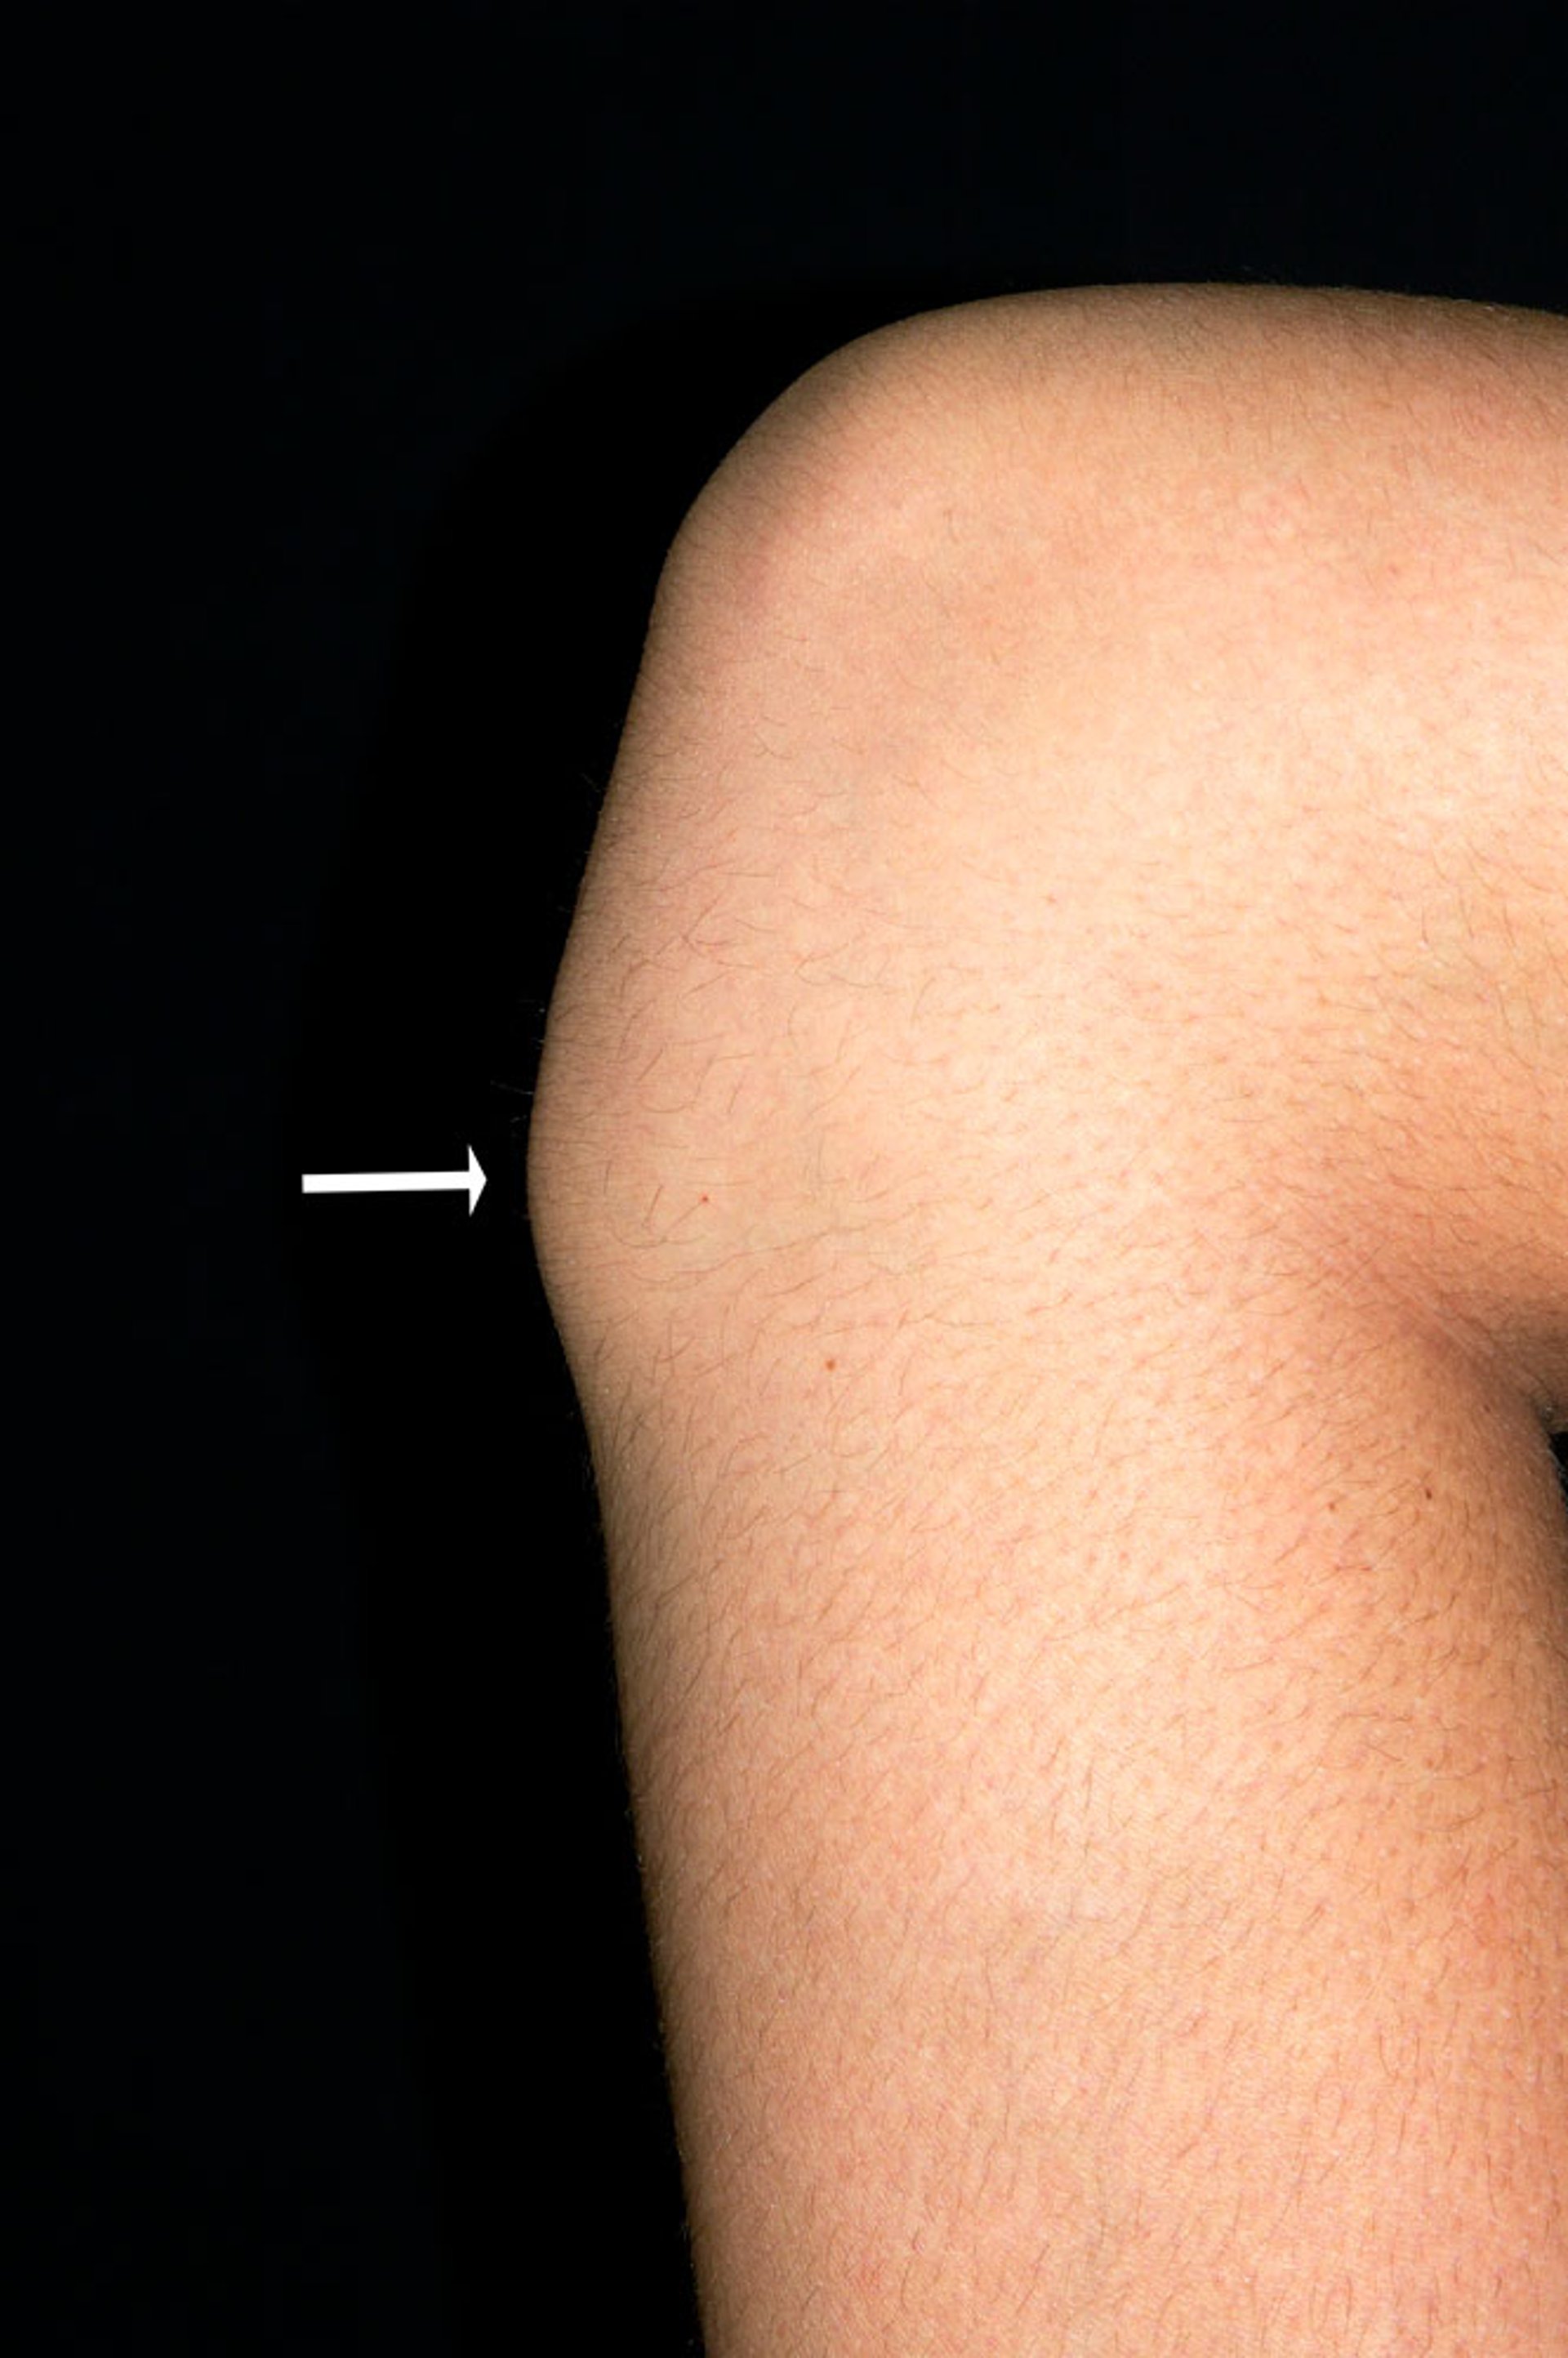

This photo shows a bony bump over the tibial tubercle (arrow) just below the knee of an adolescent male. The bump is due to Osgood-Schlatter disease.